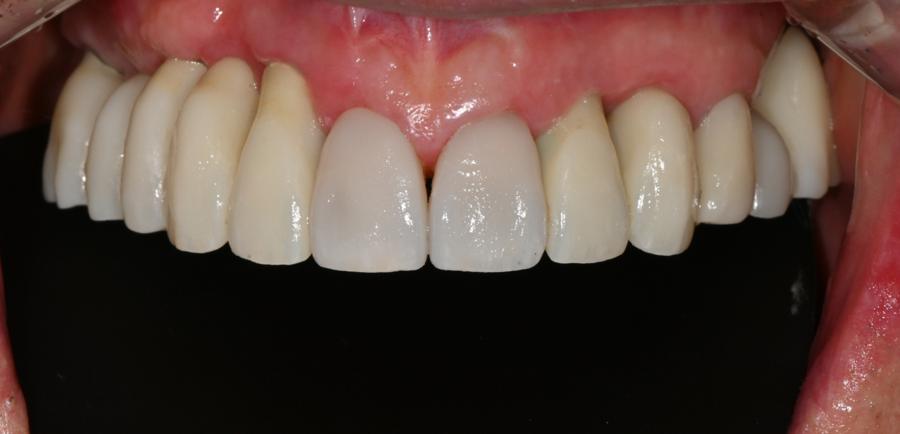

최종 오브제로 라미네이트 장착 (OVZERO)

기공소에서 완성된 최종 라미네이트는

자연광처럼 은은한 투명감과 생치에 가까운 질감,

그리고 시니어 환자분의 입술 라인과

자연스럽게 어울리는 형태로 제작되었습니다.

장착 후 환자분은 거울을 보며

“10년은 젊어진 것 같다”며 환하게 웃으셨습니다.

특히 앞니가 밝아지니

얼굴 전체가 부드럽고 환한 인상으로 바뀌었습니다.